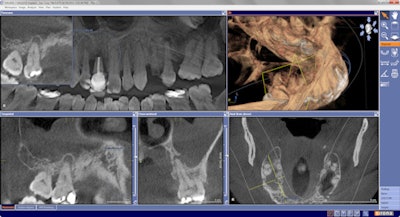

Determining what is normal versus what is diseased becomes routine with the use of cone-beam CT (CBCT) imaging. I use a Galileos CBCT system (Sirona Dental) to discover abnormal tissue by revealing and identifying unusual findings or signs in the maxillofacial anatomy of my patients.

It is quite common to scan a patient for diagnostic purposes in one area and discover pathology or atypical anatomy in a different area. An incidentaloma -- a term coined in a 2010 article in the Journal of Implant & Advanced Clinical Dentistry (April 2010, Vol. 2:3, pp. 87-92) is the "discovery of any unsuspected pathology, anomaly, dental structure (such as retained root tip, impacted tooth, or supernumerary), or deviation from the normal anatomy on a CT scan."

Extensive decay, periodontal disease (bone loss), endodontic pathology, missed canals, sinus pathology, internal resorption, and missing teeth are common findings during a complete dental examination. Enhanced imaging CBCT scans reveal these problems at such a high rate that some practices routinely scan all their patients, because many of these problems go unseen in limited 2D radiographs. I am not a proponent of that practice.

I will present a number of scans that illustrate extensive asymptomatic pathology and bony destruction that goes undetected, unrecognized, or neglected by dentists and patient alike. Assessing 3D scans with the patient improves communication and increases case acceptance. Patients with low dental IQ can be informed and persuaded that deleterious pathologies need to be removed and tissue restored.